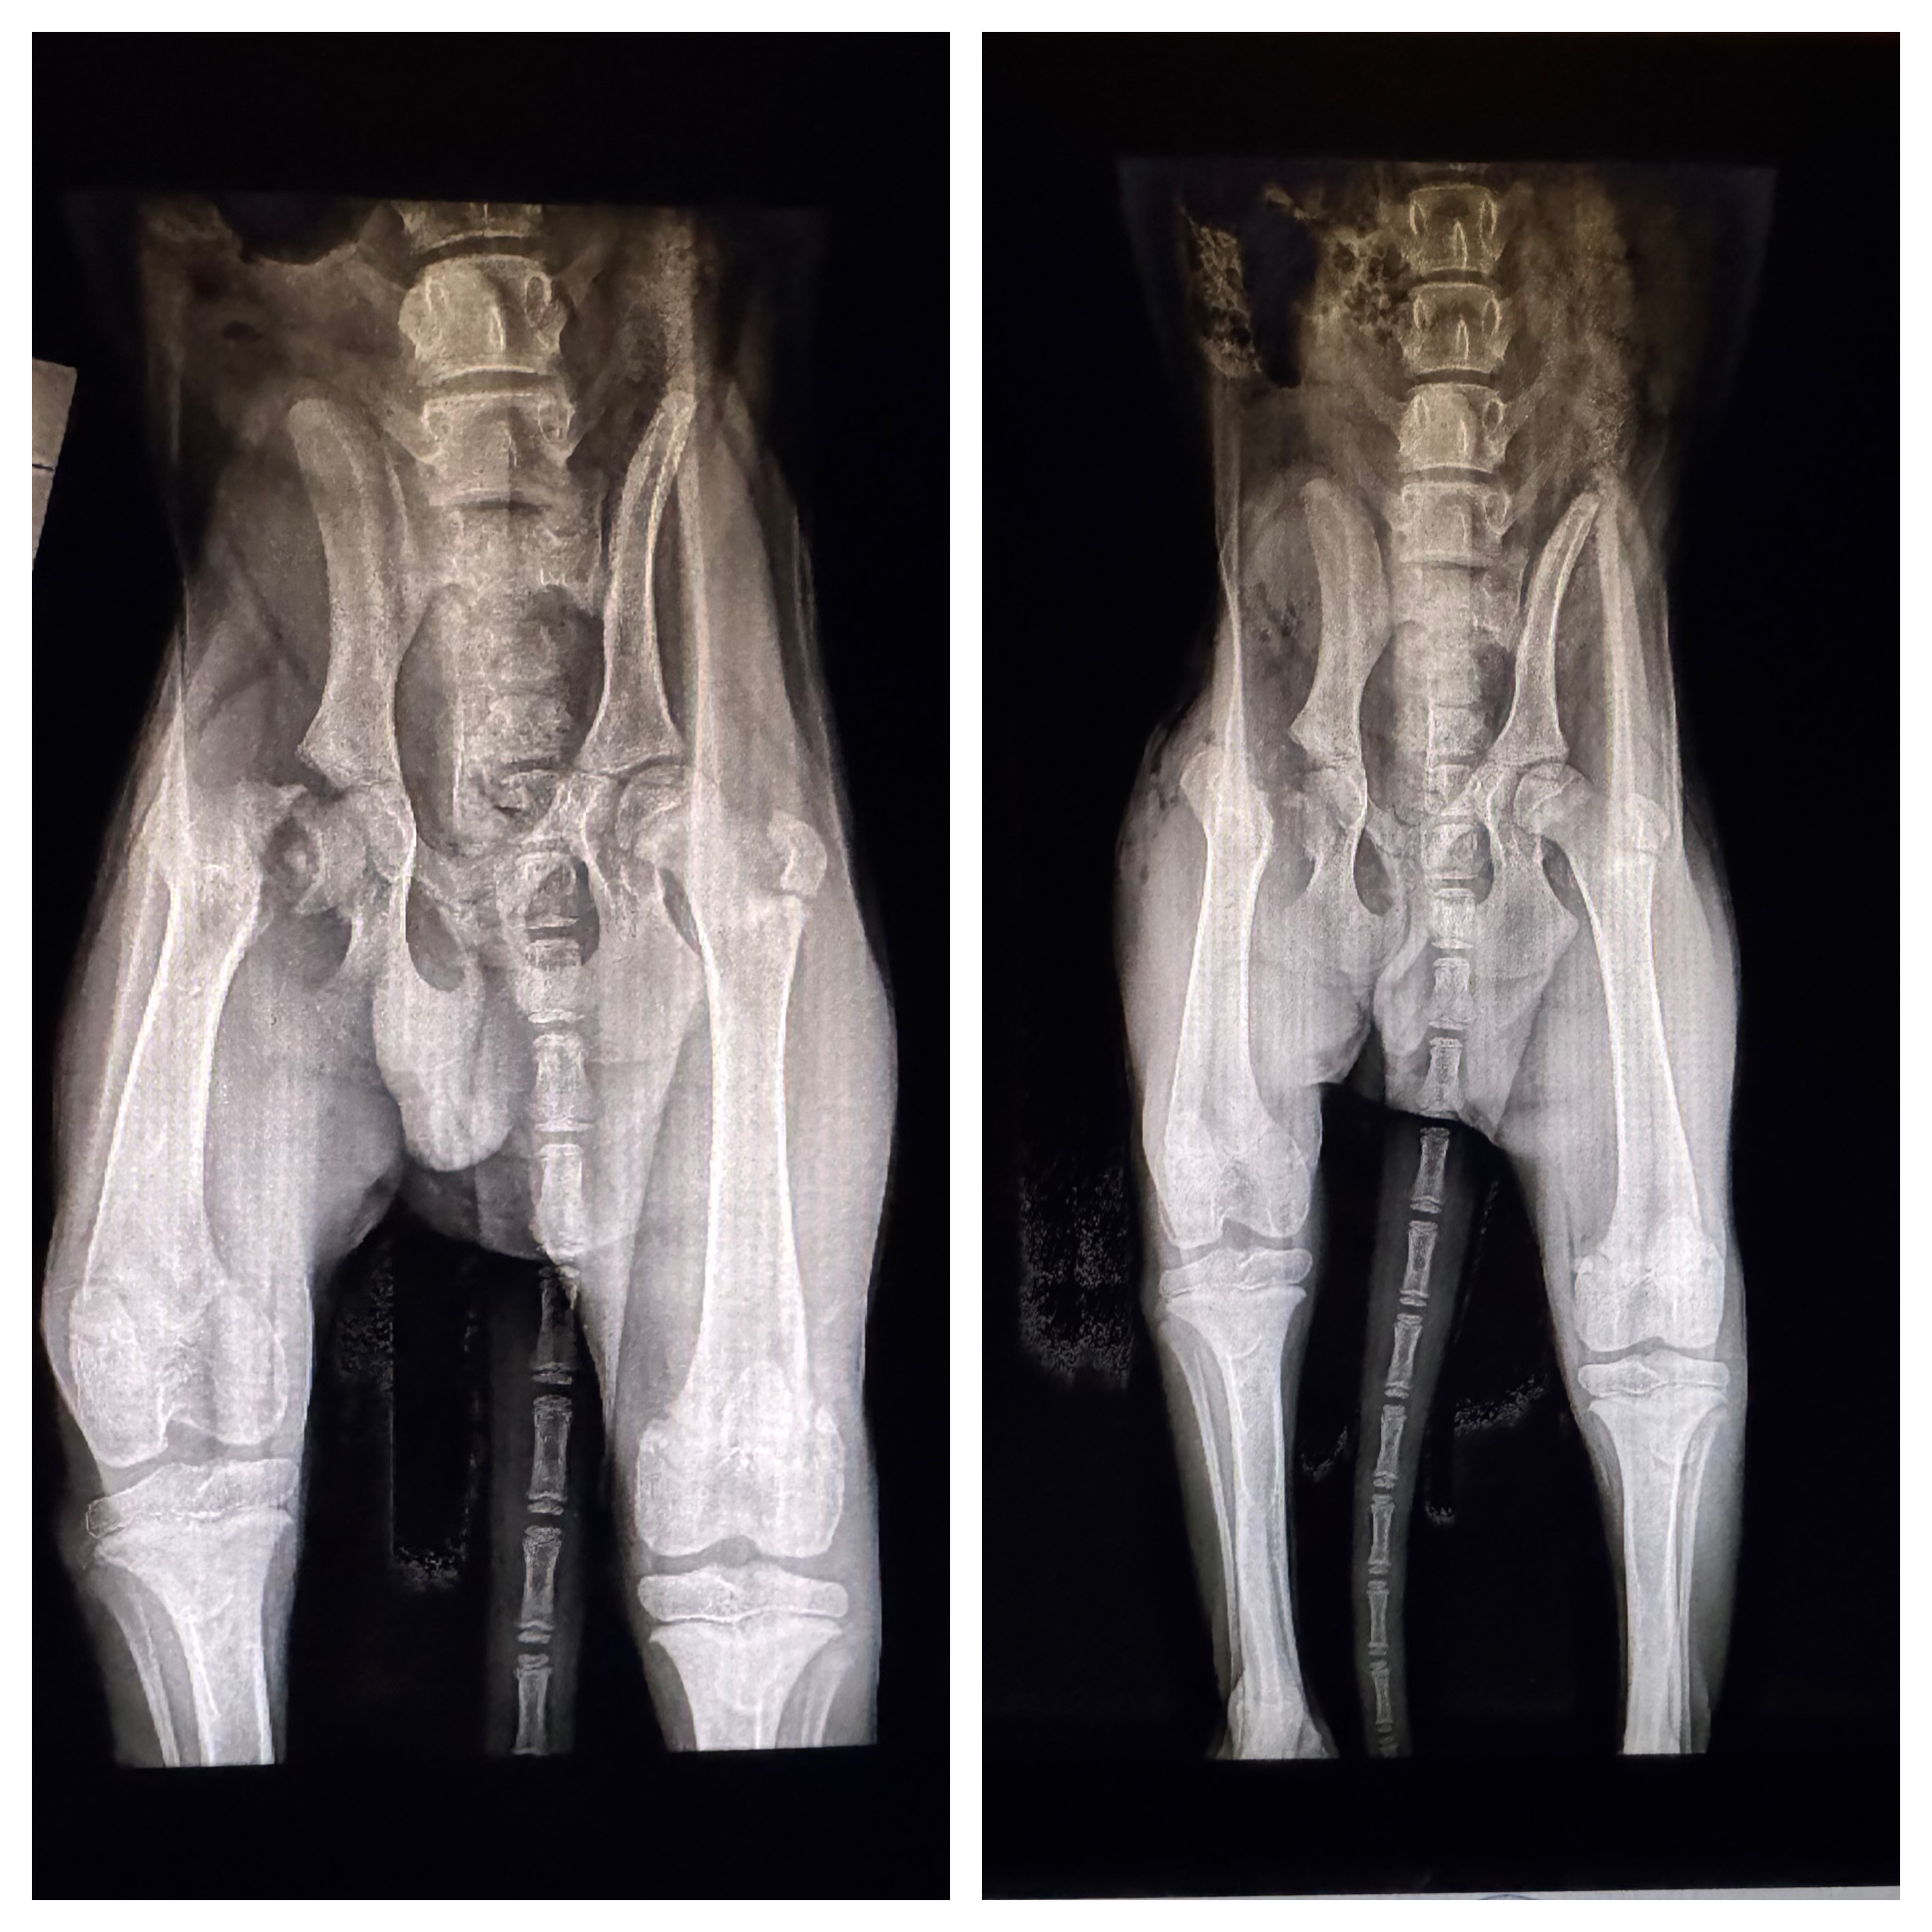

Lego is a 5-month-old black Lab mix who has overcome a difficult start to life with incredible strength and sweetness. After coming into rescue with a fractured hip and undergoing FHO surgery, Lego is now fully healed and thriving in his foster home.